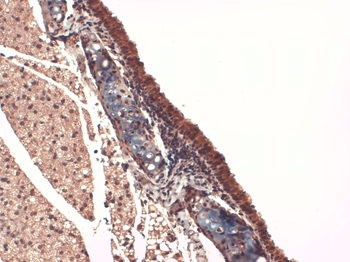

IHC-P image of mouse ovary vessel tissue using anti-NIS (2.5 ug/ml)

Immunofluorescence analysis of mouse ovary tissue using anti-NIS (2.5 ug/ml)